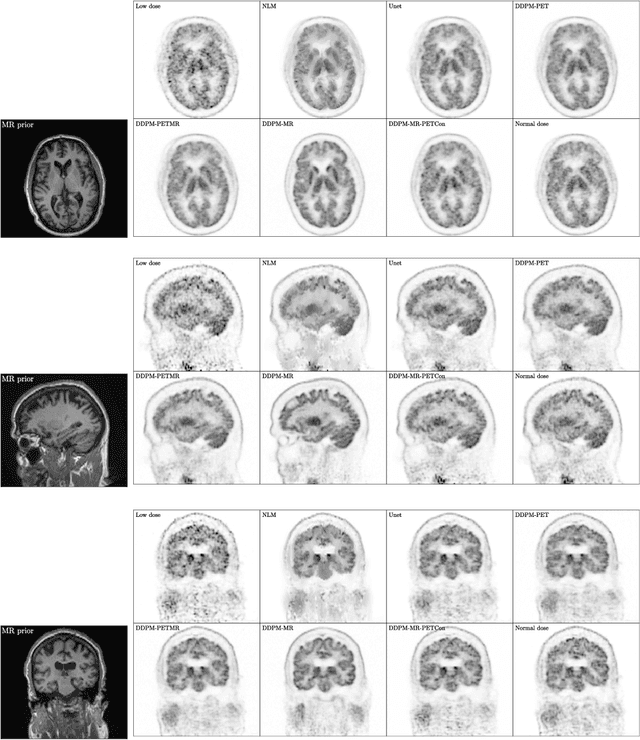

Abstract:Due to various physical degradation factors and limited counts received, PET image quality needs further improvements. The denoising diffusion probabilistic models (DDPM) are distribution learning-based models, which try to transform a normal distribution into a specific data distribution based on iterative refinements. In this work, we proposed and evaluated different DDPM-based methods for PET image denoising. Under the DDPM framework, one way to perform PET image denoising is to provide the PET image and/or the prior image as the network input. Another way is to supply the prior image as the input with the PET image included in the refinement steps, which can fit for scenarios of different noise levels. 120 18F-FDG datasets and 140 18F-MK-6240 datasets were utilized to evaluate the proposed DDPM-based methods. Quantification show that the DDPM-based frameworks with PET information included can generate better results than the nonlocal mean and Unet-based denoising methods. Adding additional MR prior in the model can help achieve better performance and further reduce the uncertainty during image denoising. Solely relying on MR prior while ignoring the PET information can result in large bias. Regional and surface quantification shows that employing MR prior as the network input while embedding PET image as a data-consistency constraint during inference can achieve the best performance. In summary, DDPM-based PET image denoising is a flexible framework, which can efficiently utilize prior information and achieve better performance than the nonlocal mean and Unet-based denoising methods.